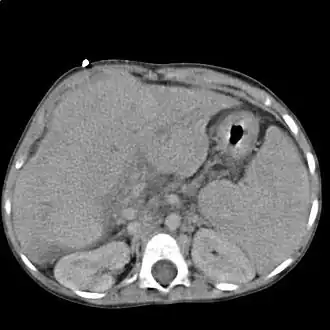

|

Cirrosis de hígado visto axialmente con tomografía computada de abdomen | ||